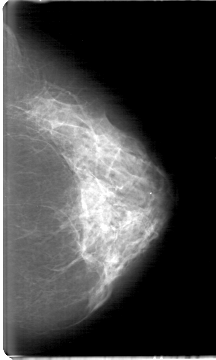

D_4088_1.RIGHT_CC

RIGHT_CC LINES 5386 PIXELS_PER_LINE 2971 BITS_PER_PIXEL 12 RESOLUTION 43.5 NON_OVERLAY